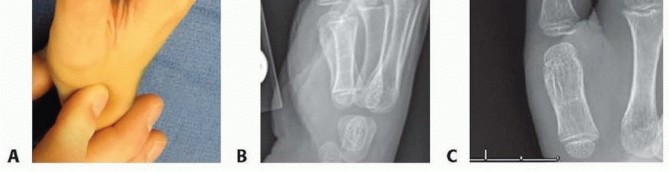

Illustration of clinodactyly surgical treatment - Dr. Mohammed Hutaif

• ![Image](\\media\\upload\\30e49631-99be-41d9-aed7-20f6660e9f18.jpg)